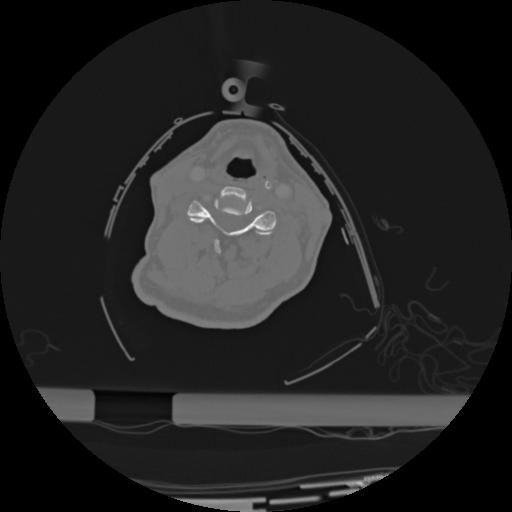

22 ANGIO,CE,Vol,0.5,ANGIO,,